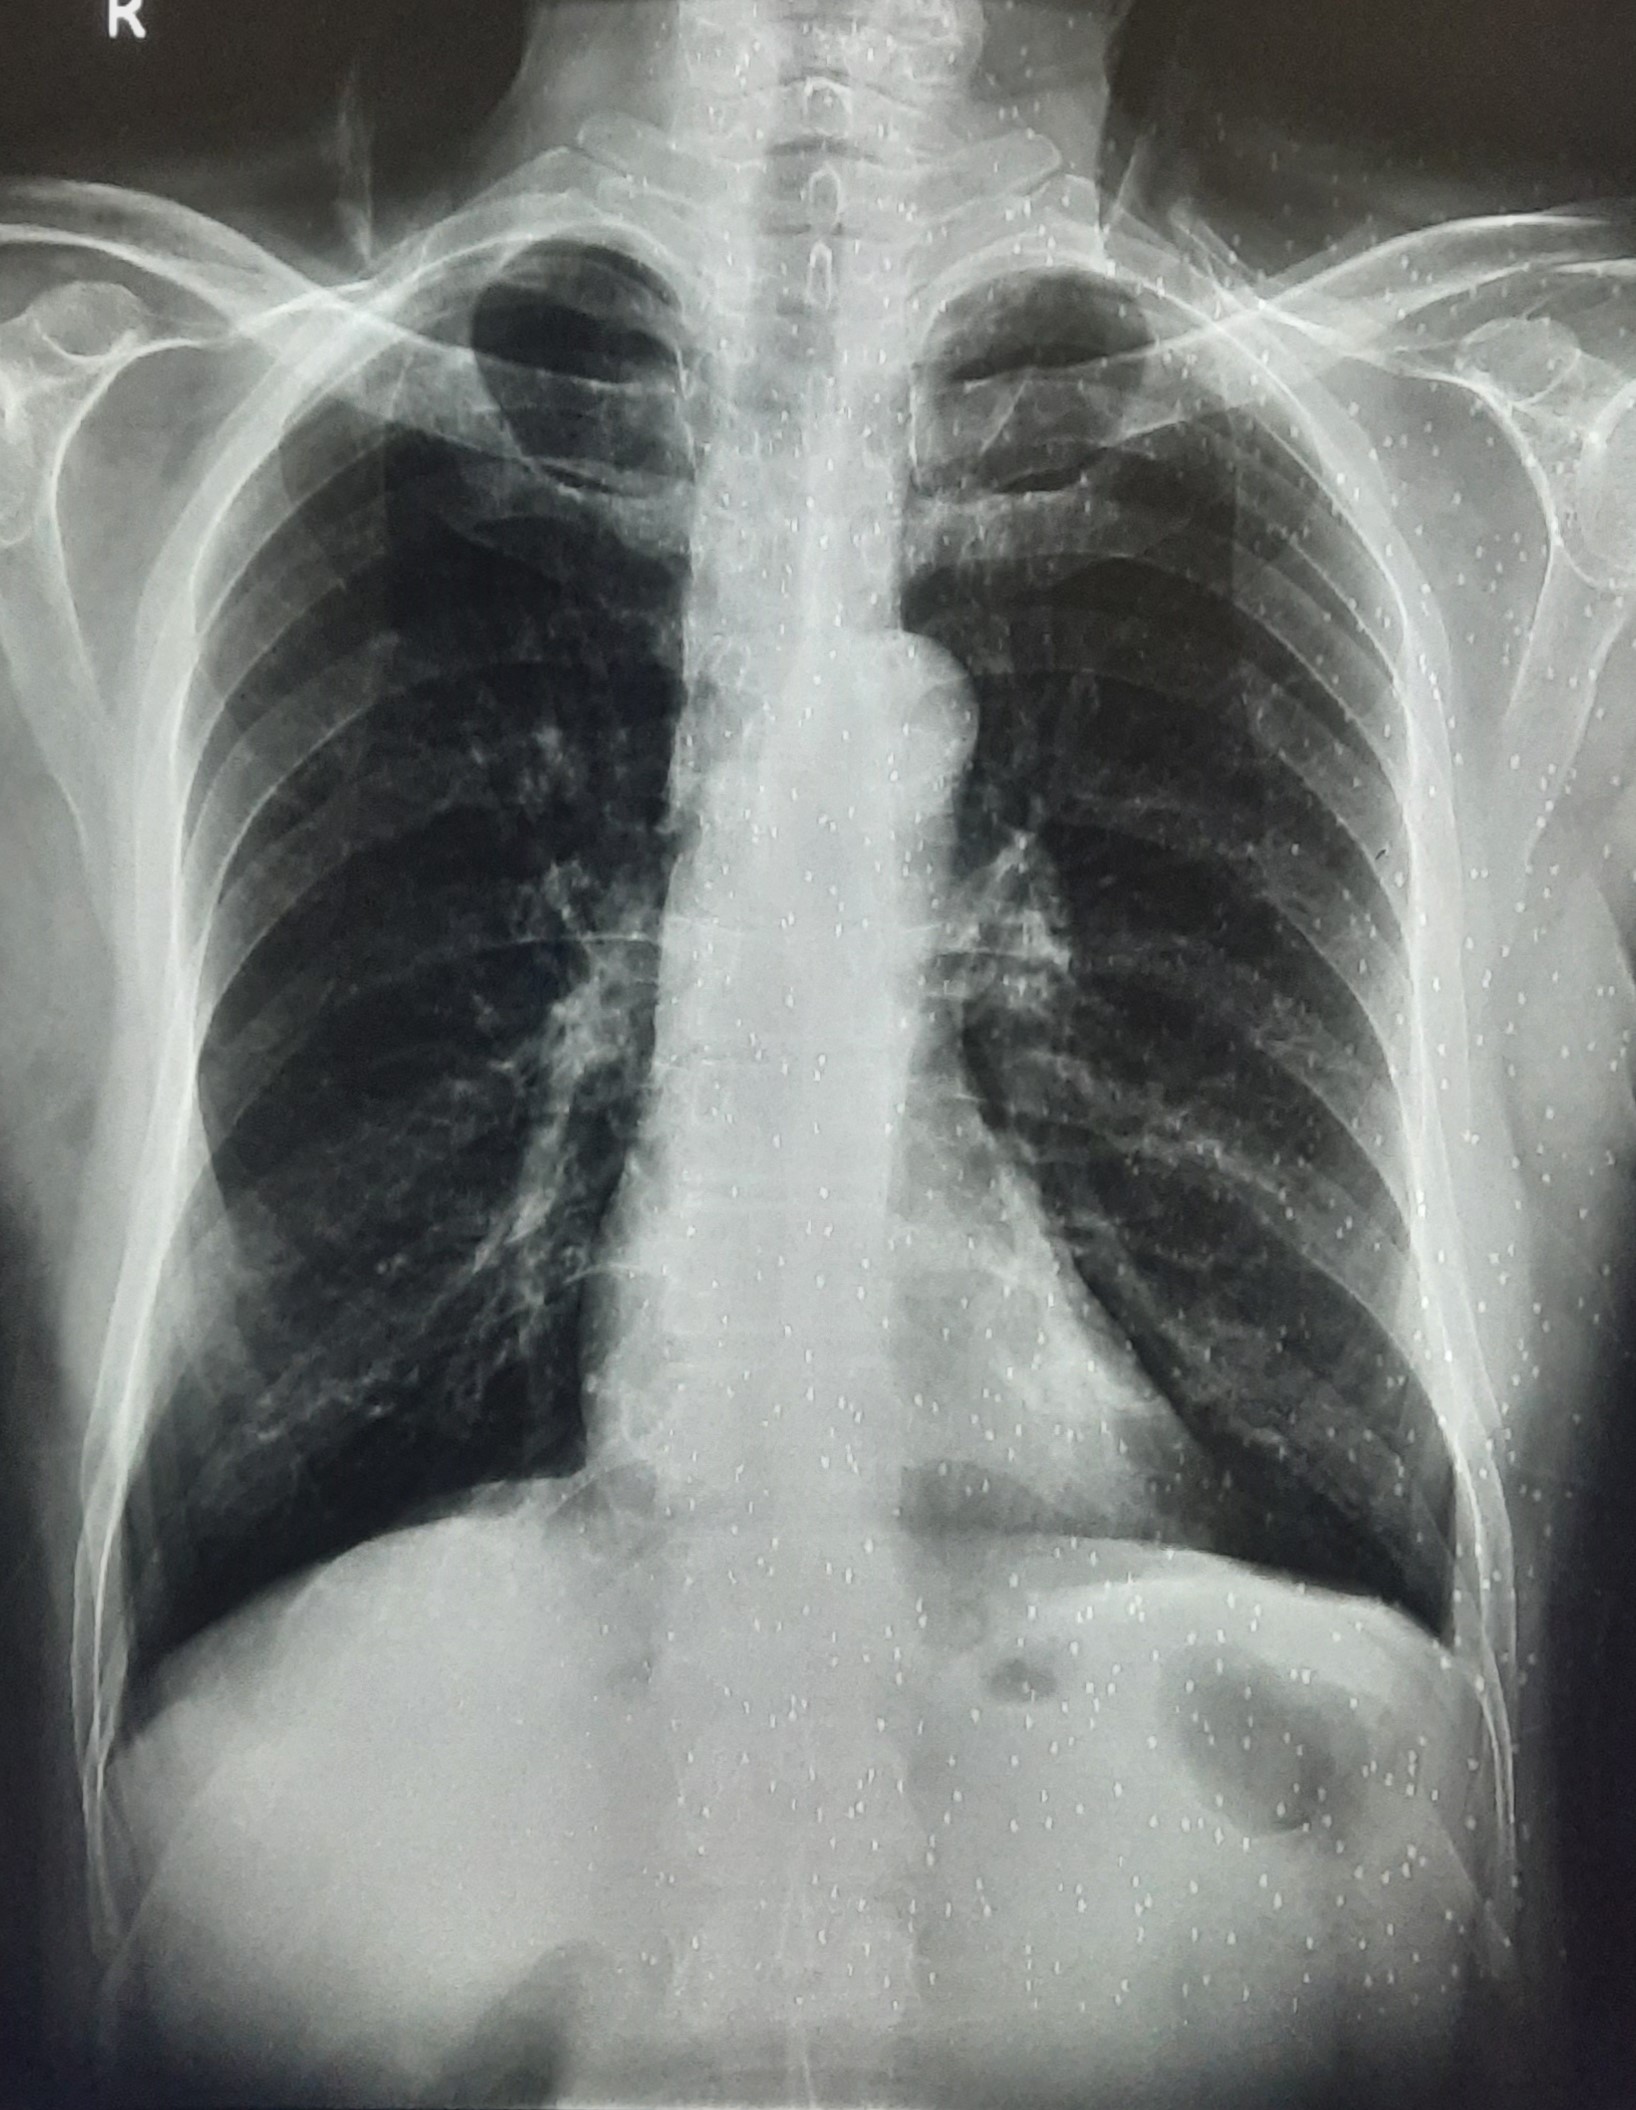

| 297 | IGGMC, Nagpur, Nagpur | P2 | 29-4175 | Sabina Parveen | Consent taken on Paper | 23 Yrs. |

Provisional Diag : PTB Reactivation

Final Diag : ? |

TB Case (Confirmed) | Bilateral Middle Lower Zone Pulmonary TB | Abnormality visible on x-ray |